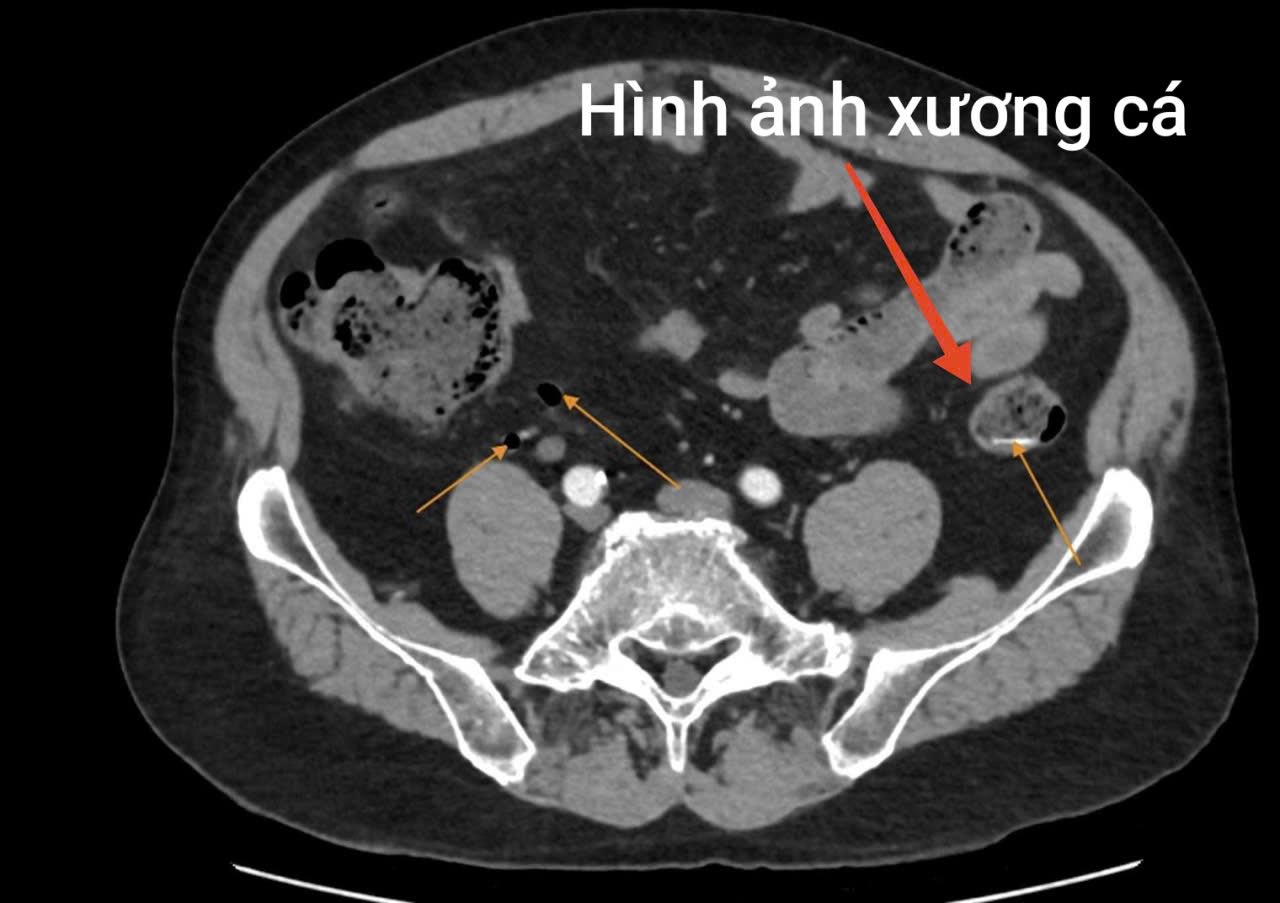

Kết quả xét nghiệm và chẩn đoán hình ảnh cho thấy tình trạng nguy hiểm của bệnh nhân: chỉ số bạch cầu tăng cao (14.6 10^9/L), hình ảnh nhiều dị vật hình xương cá nằm ngang đoạn ruột non. Kèm theo vị trí đại tràng xuống vùng hố chậu phải trong lòng có một dải tăng tỷ trọng (kích thước 24 x 6mm). Bệnh nhân được chẩn đoán thủng ruột non do dị vật, với bệnh nền bệnh phổi tắc nghẽn mạn tính và được chỉ định phẫu thuật cấp cứu.

Trong quá trình mổ, ê kíp phẫu thuật phát hiện ổ bụng bẩn nặng, nhiều giả mạc, dịch ổ bụng đục, tập trung ở hạ vị – hố chậu phải. Tại vị trí ruột non cách góc hồi manh tràng khoảng 1 mét, có dị vật hình xương cá dài khoảng 4cm chọc thủng ruột non tạo thành 01 lỗ thủng đường kính khoảng 0,5cm.